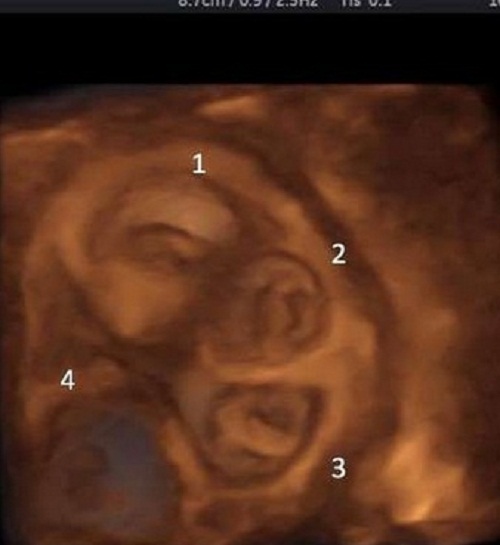

| Bác sĩ phát hiện có 5 tim thai khi siêu âm cho người phụ nữ 30 tuổi |

Cụ thể, người phụ nữ này đã mang thai được 8 tuần nhưng điều kỳ lạ là bác sĩ nghe thấy có 5 tim thai.

Sau khi kiểm tra kỹ lưỡng, các bác sỹ phát hiện cô có bào thai đang phát triển ngoài tử cung. Họ khuyên cô nên để lại 2 bào thai thôi nếu không muốn nguy hiểm đến tính mạng bởi đây là trường hợp hiếm.